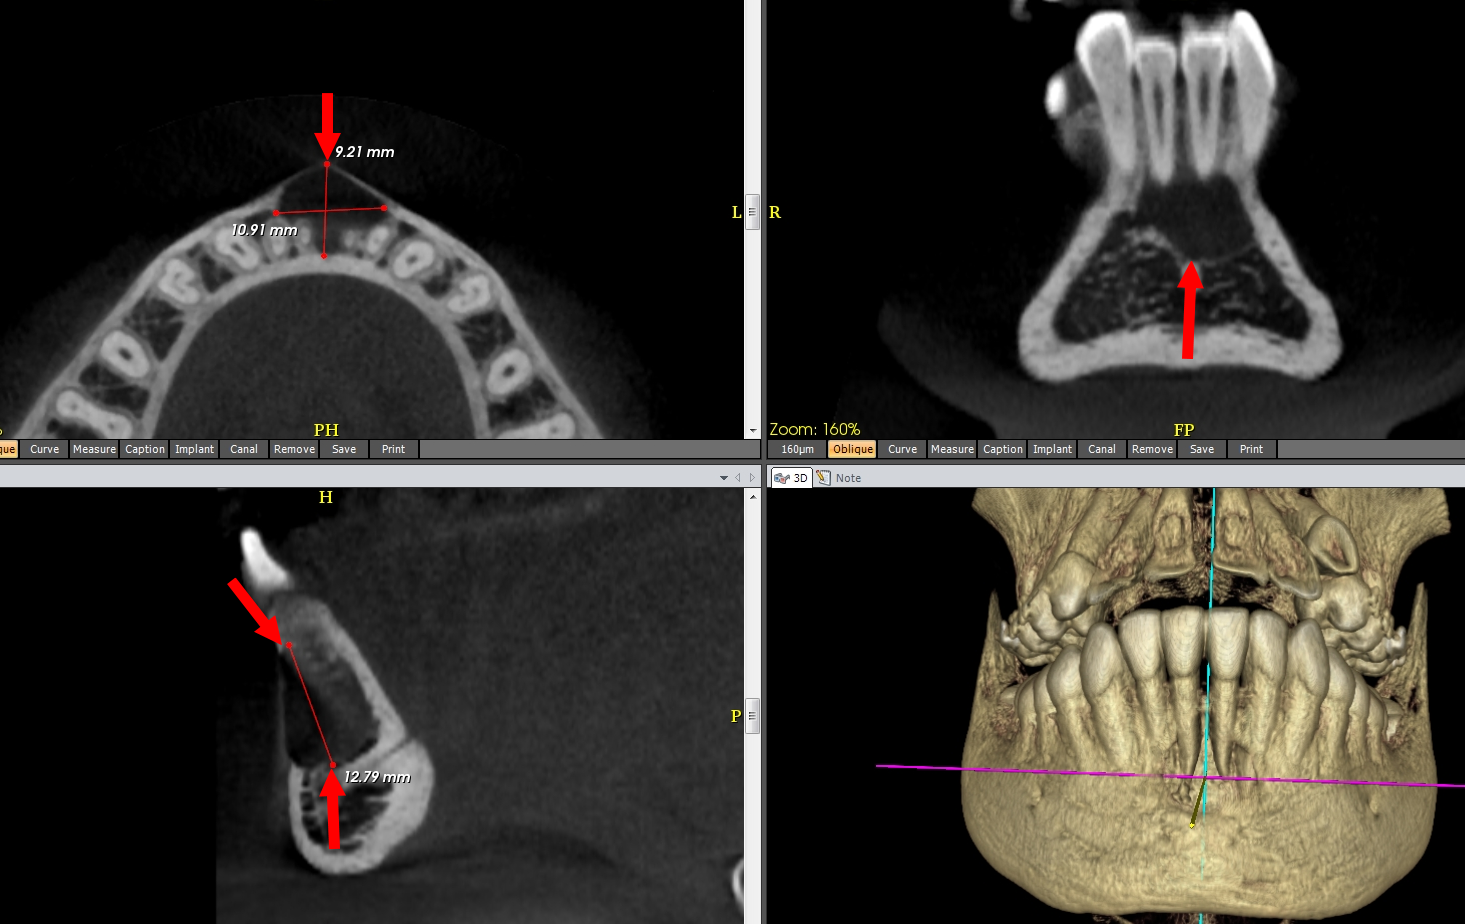

CLINIQUE : Patiente de 14 ans. Asymptomatique. Découverte fortuite sur une panoramique dentaire d’un kyste mandibulaire antérieur de 12 mm de grand axe. Absence de notion de traumatisme récent ou de l’enfance. Tests de vitalité des dents du bloc incisivo- canin mandibulaire positifs. (Patiente du Dr Jean-Luc Charrier).

1. Kyste :

– Unique,

– Sans calcification en son sein,

– À limites régulières,

– Sans paroi individualisable,

– Soufflant la corticale vestibulaire,

– Centré par les apex de 11 et 21,

– Qui ne sont pas résorbés.

• Signes radiologiques (mieux définis par cone beam).

C’est typiquement une lacune purement liquidienne, sans calcification, plus ou moins bien limitée, volontiers festonnée ou de forme triangulaire à sommet supérieur, entre les apex d’une symphyse mandibulaire, parfois de siège prémolomolaire ou plus postérieur,

– le plus souvent solitaire, de taille limitée, rarement multiple et/ou de grande taille,

– amincissant ou soufflant les corticales, surtout vestibulaire,

– sans résorption apicale des dents adjacentes,

– associée à de fines cloisons osseuses dans 1/3 des cas et rarement plus ou moins opaque.